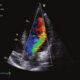

Para diagnosticar esta afección, se utilizan varios métodos. La ecocardiografía es fundamental, ya que permite visualizar la válvula aórtica y evaluar el grado de regurgitación. El electrocardiograma (ECG) puede mostrar signos de sobrecarga en el ventrículo izquierdo, mientras que la radiografía de tórax puede revelar un agrandamiento del corazón o una dilatación de la aorta. En algunos casos, se emplean la resonancia magnética (RM) o la tomografía computarizada (TC) para obtener una visión más detallada de la aorta y la válvula.